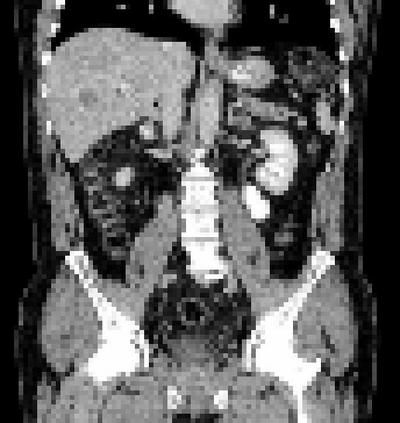

Due to the constraints of the imaging device and high cost in operation time, computer tomography (CT) scans are usually acquired with low intra-slice resolution. Improving the intra-slice resolution is beneficial to the disease diagnosis for both human experts and computer-aided systems. To this end, this paper builds a novel medical slice synthesis to increase the between-slice resolution. Considering that the ground-truth intermediate medical slices are always absent in clinical practice, we introduce the incremental cross-view mutual distillation strategy to accomplish this task in the self-supervised learning manner. Specifically, we model this problem from three different views: slice-wise interpolation from axial view and pixel-wise interpolation from coronal and sagittal views. Under this circumstance, the models learned from different views can distill valuable knowledge to guide the learning processes of each other. We can repeat this process to make the models synthesize intermediate slice data with increasing inter-slice resolution. To demonstrate the effectiveness of the proposed approach, we conduct comprehensive experiments on a large-scale CT dataset. Quantitative and qualitative comparison results show that our method outperforms state-of-the-art algorithms by clear margins.